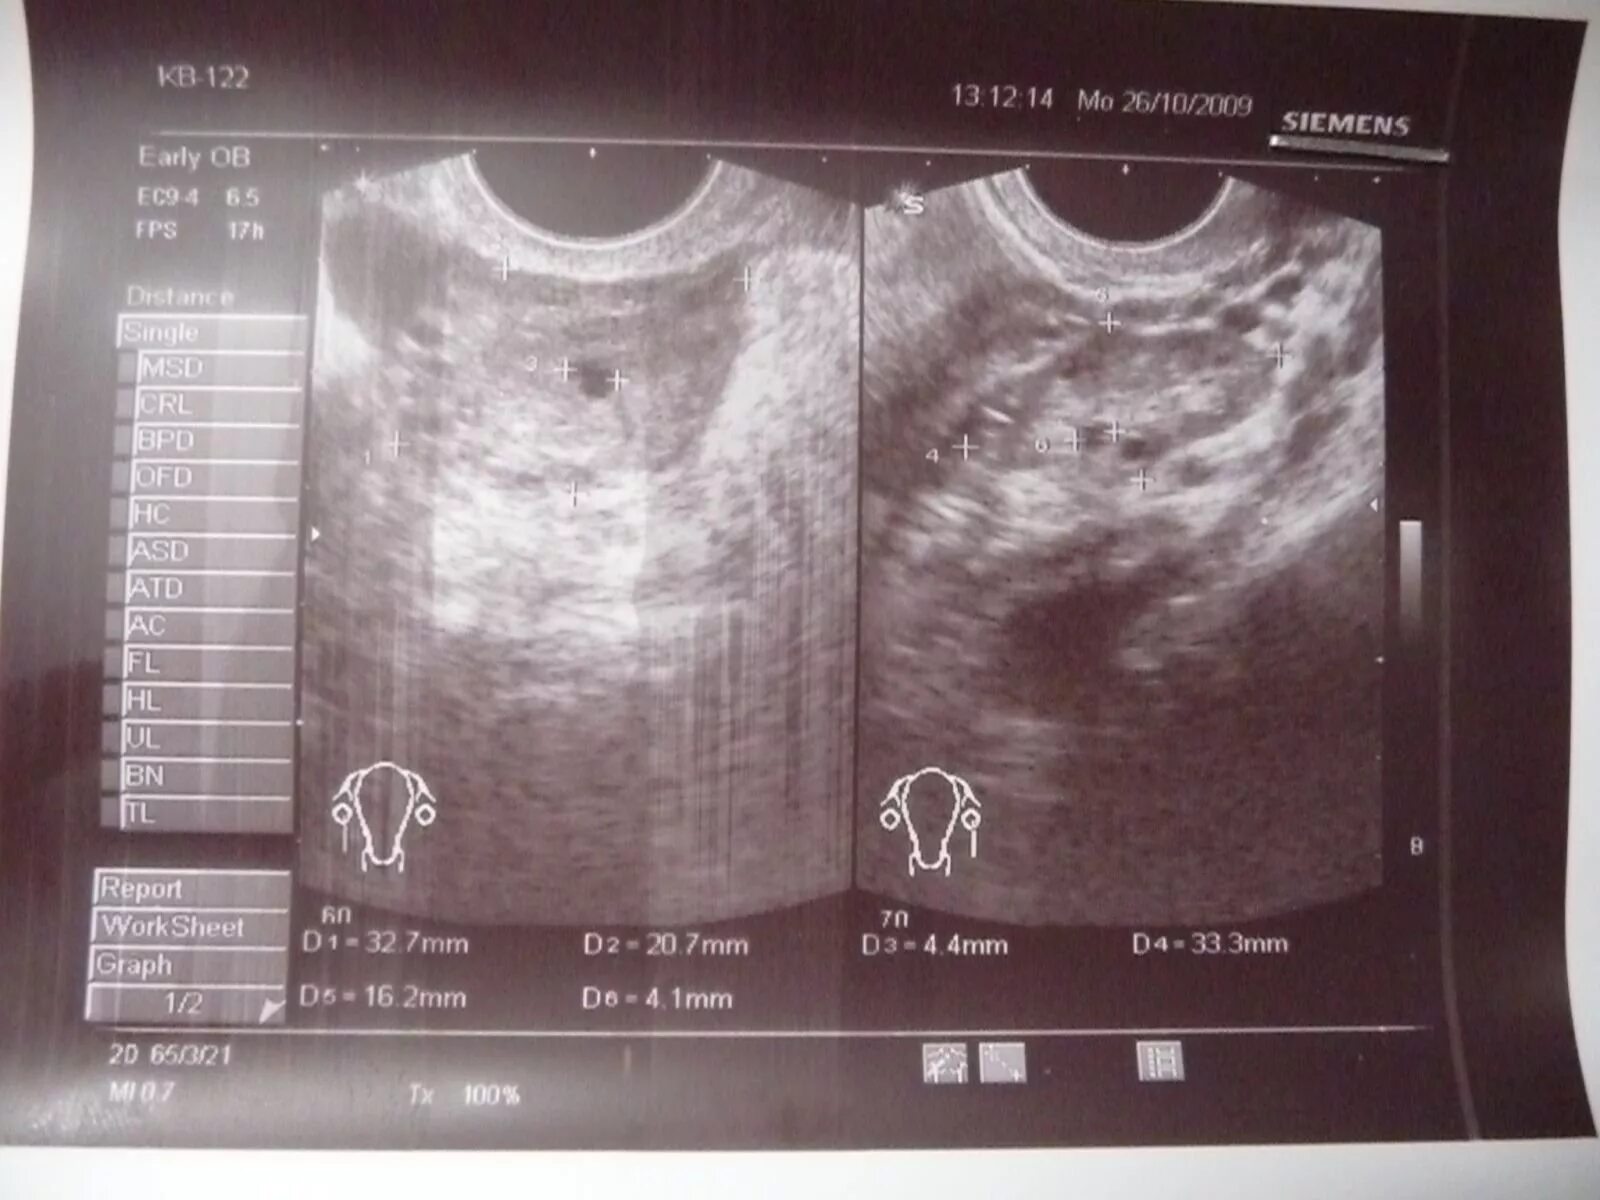

Эндометрий 9 мм